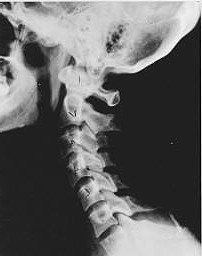

Phase Three Subluxation Degeneration

Phase Three Subluxation Degeneration is caused by subluxations that have been continuing on for between 40 and 65 years.  This phase has all of the attributes of the previous phases, only worse.  The curvatures are abnormal, the disc spaces are vastly decreased and changed.  Calcium changes on the spine are abundant in this phase.  Normally, people in phase three have a restricted range of motion and probably exhibit symptoms of some kind.  In phase three the vertebrae show obvious changes and mutations in shape.  Projections made of calcium, sometimes referred to as “spurs or lipping”, can be readily seen on x-ray.  Chiropractic reconstructive care for patients in phase three ranges from 2.5 years to 3.5 years.  This does not mean that at the end of this time that any or all of the calcium changes will be gone.  In many instances the body adapts to the presence of the calcium and positive changes can only be measured from a functional standpoint.  As before, if Phase Three Subluxation Degeneration is left unchecked it slowly advances onward into the next phase.

Phase Four Subluxation Degeneration

Phase four subluxation degeneration is seen with subluxations that have been raging on uncorrected or altered for over sixty five years.  Phase four is a grave condition that will negatively affect the patients longevity and quality of life.  The massive amount of neurological damage caused by years of subluxation that have lead to phase four are probably taking a serious toll on this person’s health status.  X-rays in phase four show serious severe structural changes.  Vertebrae exhibit massive calcium changes, disc spaces appear blurred, and the bones themselves appear fused.  In this scenario the patient will have a severe restriction of range of motion in addition to probably a number of other health issues.  Reconstruction may not be possible in phase four, but care can be directed to some reduction in subluxation with the goal of improvement in the quality of life remaining.  Patients in Phase Four Subluxation Degeneration have a serious situation both structurally and neurologically, but they are certainly not beyond hope.  Many patients in phase four report significant improvements in symptoms, conditions, mobility and quality of life.